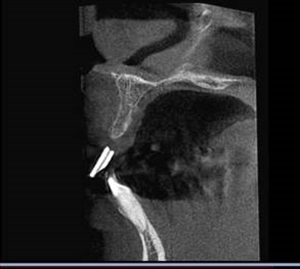

術後のCTです。

リッジエクスパンションはドリルを使わないので患者さんにも優しく外科的侵襲も少ない良い方法です。 |